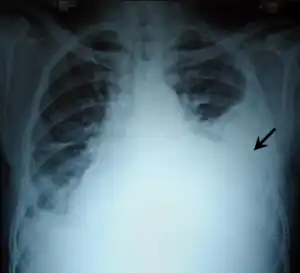

Anteroposterior chest X-ray of a pleural effusion. The A arrow shows fluid layering in the right pleural cavity. The B arrow shows the normal width of the lung in the cavity

When a pleural effusion has been determined to be exudative, additional evaluation is needed to determine its cause, and amylase, glucose, pH and cell counts should be measured.

The most common causes of exudative pleural effusions are bacterial pneumonia, cancer (with lung cancer, breast cancer, and lymphoma causing approximately 75% of all malignant pleural effusions), viral infection, and pulmonary embolism.